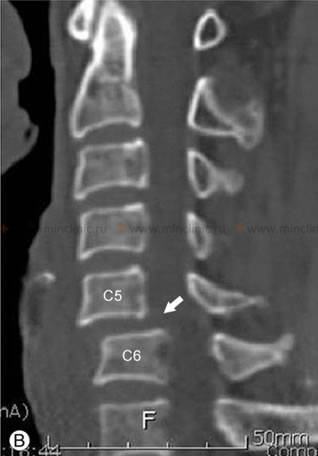

На компьютерной томографии (КТ) шейного отдела позвоночника видно выпрямление лордоза и смещение тела С5 позвонка вперёд относительно С6 (спондилолистез указан стрелкой) при нестабильности позвоночника.